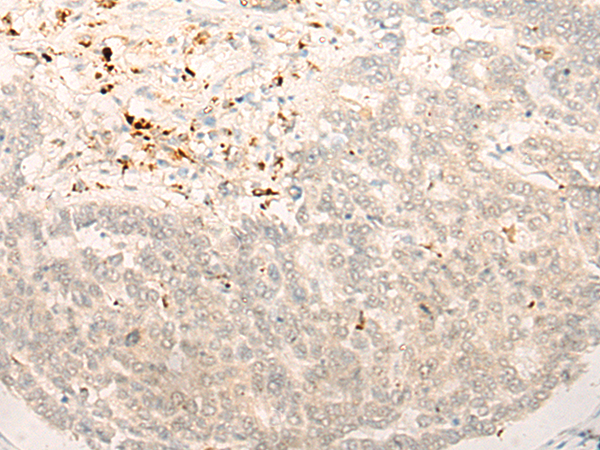

分类: 科研抗体货号: P06380别名: RRP44; dis3p; EXOSC11; KIAA1008; 2810028N01Rik应用: IHC反应种属: Human